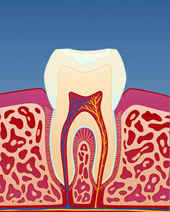

figur II